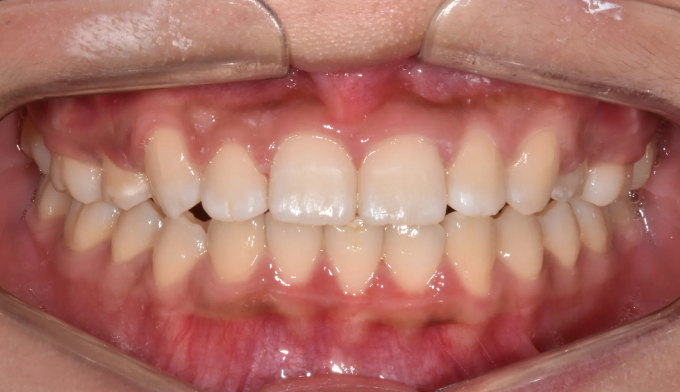

윗니가 아랫니를 많이 덮는 과개교합과 더불어 잇몸이 많이 보이는 거미스마일 환자입니다.

약간의 돌출감도 보이고 있습니다.

윗니만 양쪽 작은어금니 발치를 통해 문제점들을 해결하기로 합니다.